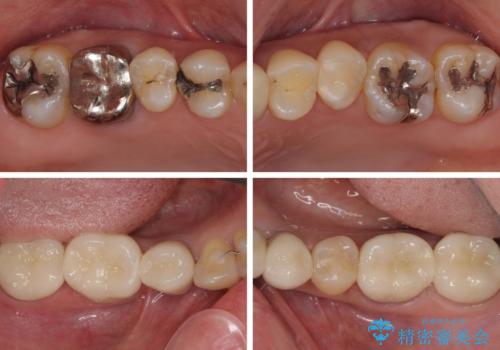

他にも奥歯の咬み合わせに問題があったので、全顎的な矯正治療を行い、前歯以外にも口を開けたときに目立つ奥の銀歯をセラミッククラウンにて補綴治療を行うこととしました。

前歯の横幅が大きいことも気になっていたので、矯正治療で前歯5本の幅をコントロールしながら移動させ、治療開始前より一回りサイズの小さいセラミッククラウンを装着することができました。